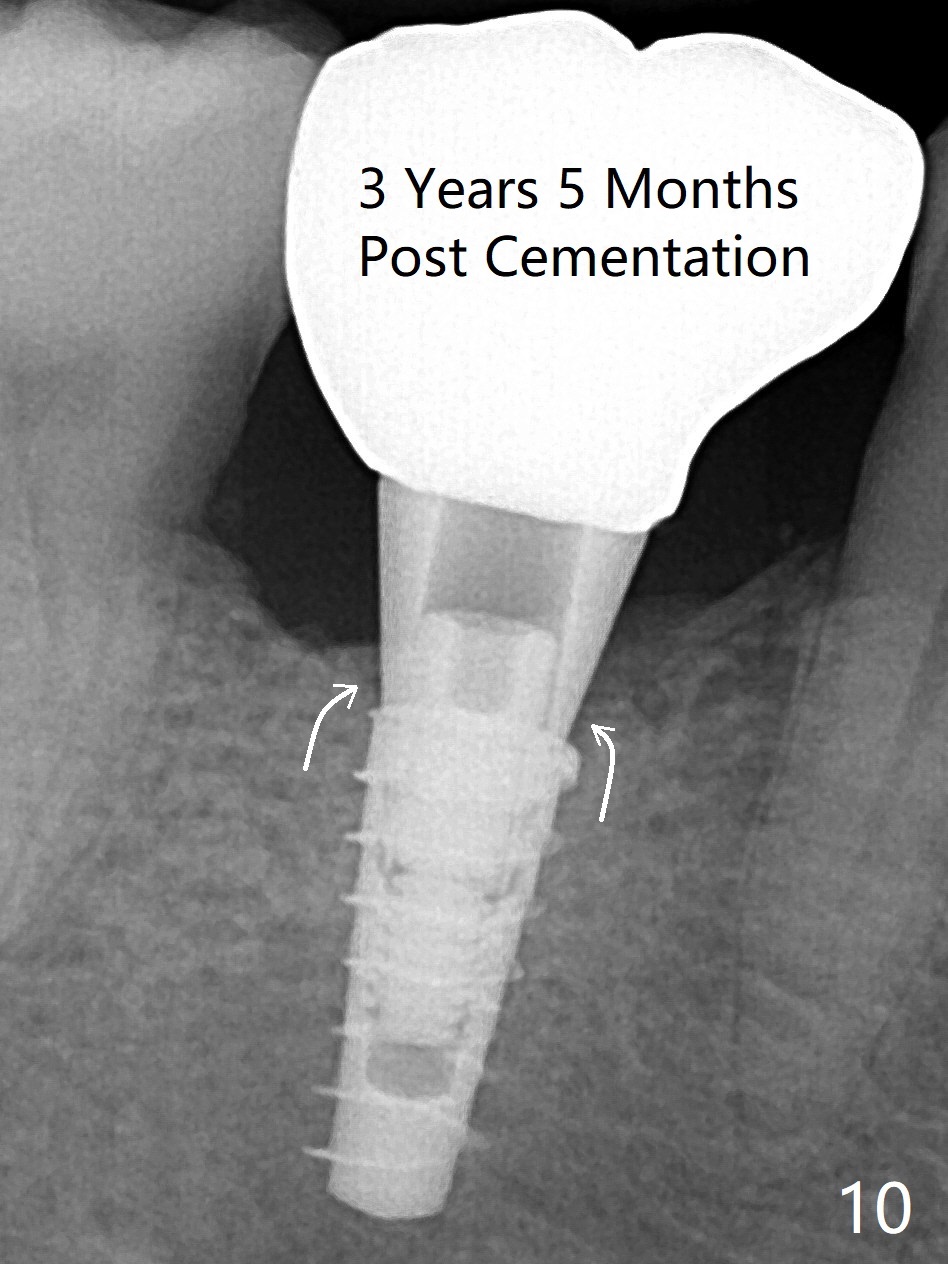

The retained deciduous tooth (lower right 2nd molar, Fig.1 T) has buccal apical infection and recession. After extraction, the initial depth of osteotomy is 11 mm over the flat socket bottom (Fig.2) without visible Mental Loop. Following 3.8 mm Magic Drill for 11 mm, a 4x11 mm dummy implant is placed partially due to hard bone; it appears that the apical osteotomy (Fig.3 yellow outline) overlaps the Mental Loop (red dashed line). For safety, a 4x9 mm IBS implant is placed with insertion torque 40 Ncm; a 5x5.7(4) mm abutment is immediately placed for an immediate provisional to cover the large socket and keep Vera graft in place (Fig.4 *). There is no postop paresthesia, probably due to the fact that the osteotomy is lingual to the Mental Loop. The provisional remains in place 7 days postop; its margin (Fig.5 arrow) covers the socket. The margin of the provisional is trimmed 1 month postop. Impression is taken nearly 3 months postop (Fig.6). The buccal plate looks atrophic 3 months postop (Fig.7 (immediately before cementation)), although there is no sign of periimplantitis. In the future, insert the immediate provisional inside of the buccal gingiva to make the buccal gingiva look bulky instead of buccal to it (Fig.5). The second drawback of placing an implant at the deciduous tooth area is that the crown is wide mesiodistally if orthodontic treatment is not rendered. Although there is lower anterior crowding, the patient declines orthodontic treatment. The bone density around the implant increases 7 months post cementation (Fig.8 *). The higher density bone seems to extend coronally 1 year 7 months post cementation (Fig.9). The dense bone apparently extends toward the abutment as well 3 years 5 months post cementation (Fig.10 curved arrows).